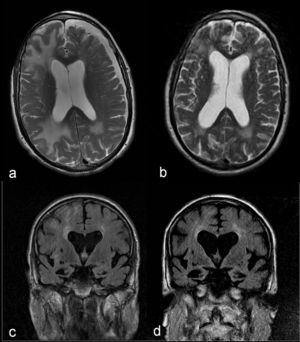

Estos resultados, unidos a la buena respuesta inicial con dexametasona, plantean como primera opción diagnóstica una AAI, por lo que se desestima practicar una biopsia y se opta por administrar un bolo de 1g de 6-metilprednisolona por vía intravenosa durante 5 días, con posterior pauta descendente de prednisona, evolucionando a una mejoría progresiva en su domicilio y recuperación de actividades previas. Un mes y medio después del inicio del cuadro se realiza una nueva RM cerebral, que muestra una notable disminución del tamaño de las lesiones en la sustancia blanca (fig. 2a y b). No obstante, cada intento de reducir la dosis de prednisona por debajo de 10mg/día empeoraba la función cognitiva, con recuperaciones parciales al aumentar la dosis. A los 7 meses del alta, la RM cerebral muestra estabilidad de las lesiones y progresión de la atrofia de hipocampos (fig. 2c y d). En el plano cognitivo ha presentado un lento deterioro (Minimental 11/30). Se establece el diagnóstico de probable AAI y probable enfermedad de Alzheimer.

Imágenes comparativas en secuencia T2 axial donde se observa una notable disminución en el tamaño de las lesiones de la sustancia blanca y resolución del higroma subdural entre la RM cerebral realizada en el momento agudo (a) y un mes y medio después (b). Imágenes comparativas en FLAIR coronal que muestran la progresión de la atrofia cerebral y de hipocampos, y la dilatación ventricular secundaria entre la RM cerebral realizada en el momento agudo (c) y 6 meses después (d).